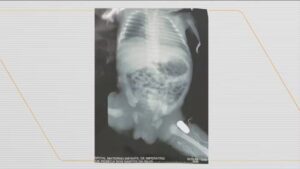

Uma adolescente de 16 anos, grávida de 9 meses, precisou realizar um parto de emergência após ser atingida por uma…